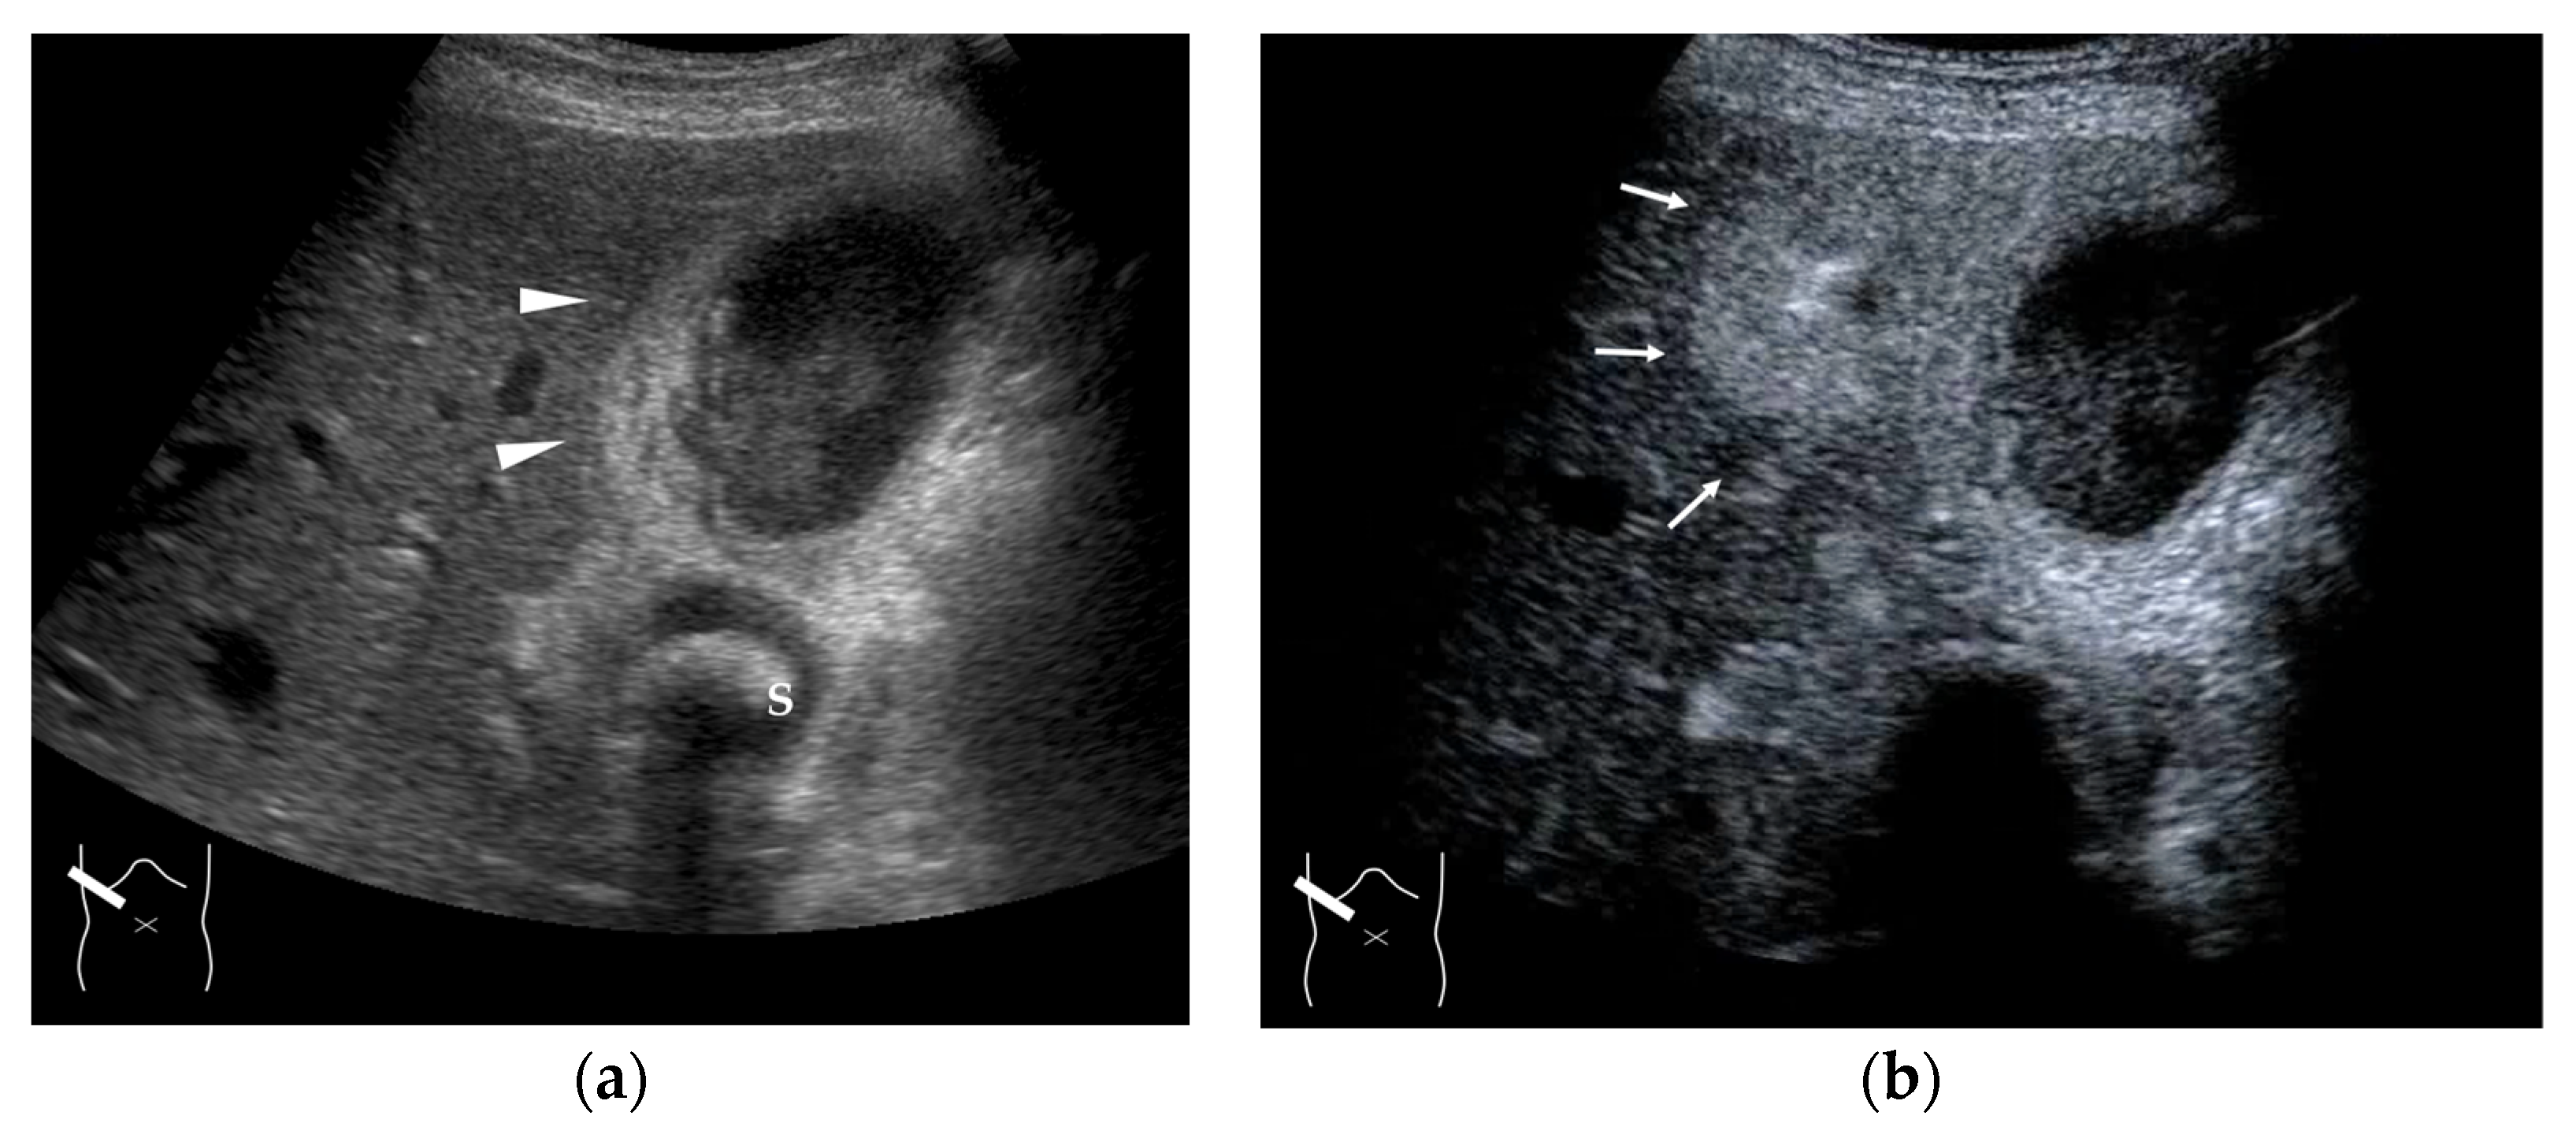

Figure 15.

Representative case of acute cholecystitis: (a) B-mode US shows the gallbladder wall to be thickened (arrow heads). (b) CEUS shows a triangular or oval hyper-enhanced zone (arrows) near the gallbladder in the arterial phase. S, gallstone.